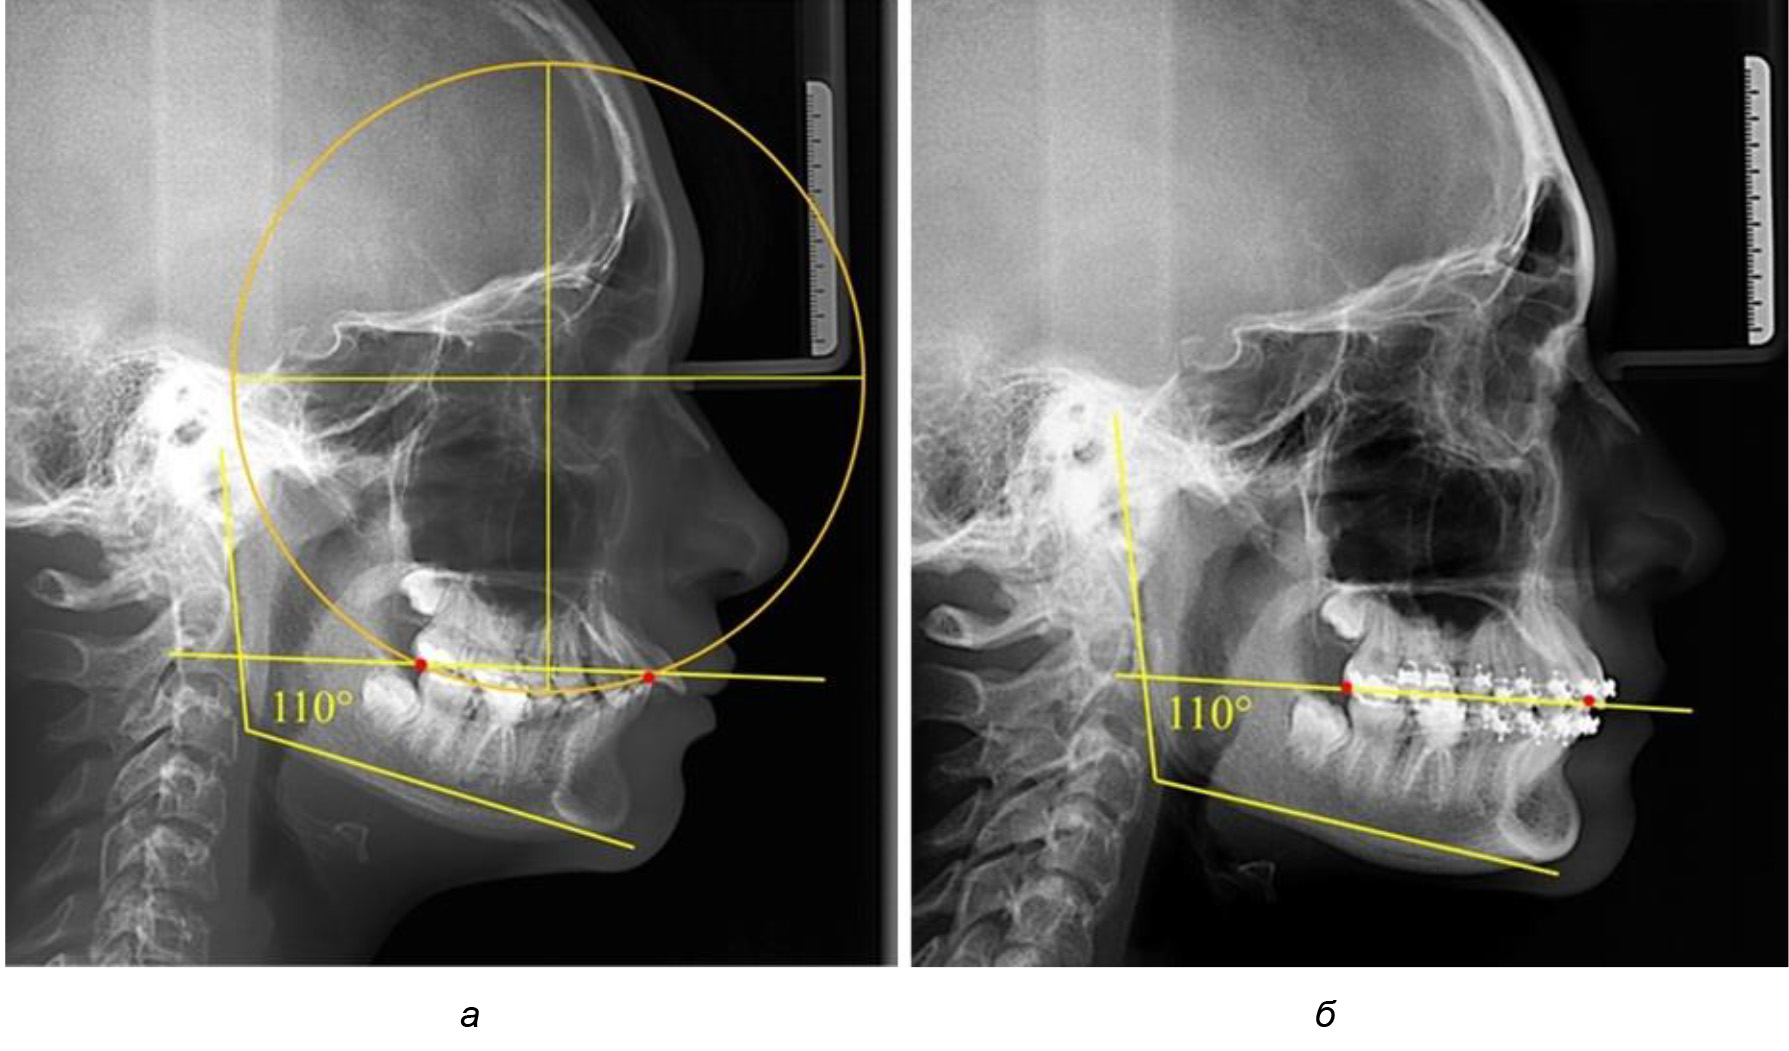

Рис. 1. Метод определения кривой Spee на ТРГ (а) и на ОПТГ (б)

При анализе латеральных ТРГ устанавливали реперный окклюзионные точки в переднем и боковом отделе. Передняя точка устанавливалась на режущем крае нижнего медиального резца, которую в клинике ортодонтии обозначают как vPOcP. Дистальная точка второго нижнего моляра обозначалась как hPOcP. Измеряли расстояние между окклюзионными точками, что определяло сагиттальный размер окклюзионной линии. Использование программ PowerPoint позволило проводить окружность, проходящую по линии смыкания зубов через окклюзионные точки. Измеряли радиус окружности. Учитывая вариабельность размеров окклюзионной линии и радиуса окружности, определяли относительный показатель через отношение радиуса круга к длине сагиттального размера окклюзионной линии. Глубину окклюзионной кривой измеряли от точки наибольшей выпуклости до окклюзионной линии (рис. 1). На ортопантомограмме (ОПТГ) также соединяли окклюзионные точки правой и левой стороны и измеряли глубину окклюзионной кривой от точки наибольшей выпуклости до окклюзионной прямой линии. Результаты глубины кривой Spee сравнивали по данным ТРГ и ОПТГ.